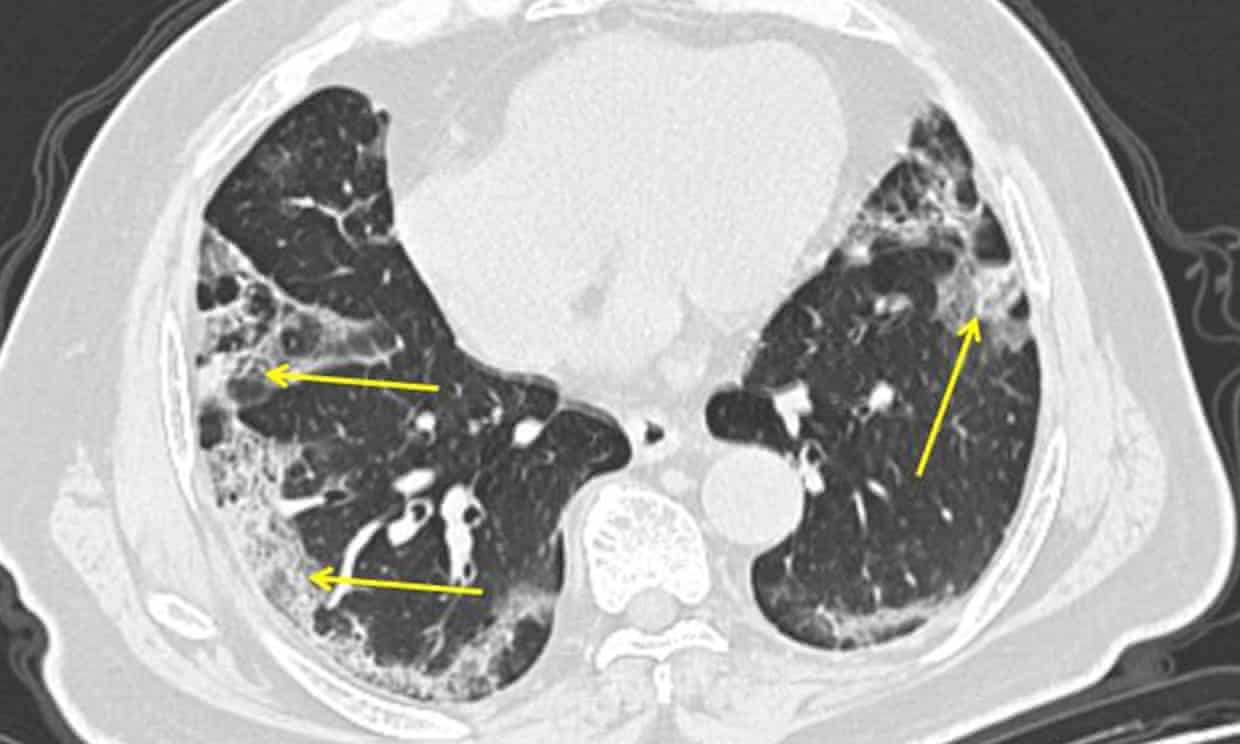

The analyses revealed two phases of infection in patients with severe COVID-19 pneumonia. The early phase is defined by high levels of virus in the lungs that trigger patients’ cells to express genes involved with the interferon pathway, a critical part of the immune response. In the later phase, virus is no longer present, but the damage to the lungs is too severe for recovery.

The team also found that there is surprisingly very little viral replication in the lungs, which suggests that the virus is mostly replicating in the nasal passages and then dropping into the lungs, where it can cause pneumonia and other complications.